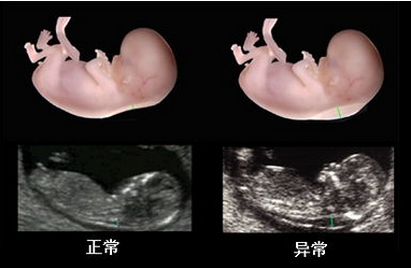

贵阳和谐阳光医院引进系统彩超,能够实时获取三维图像,超越了传统超声的限制,能立体、实时地显示人体器官的三维立体结构,为临床超声诊断提供更丰富的影像信息。

1、高端产检设备:贵阳和谐阳光医院引进的系统彩超对孕妇产前检查、各种疾病的诊断,有着现今其他超声无可替代的优越性,是目前上较为先进、科学的超声诊断仪器。